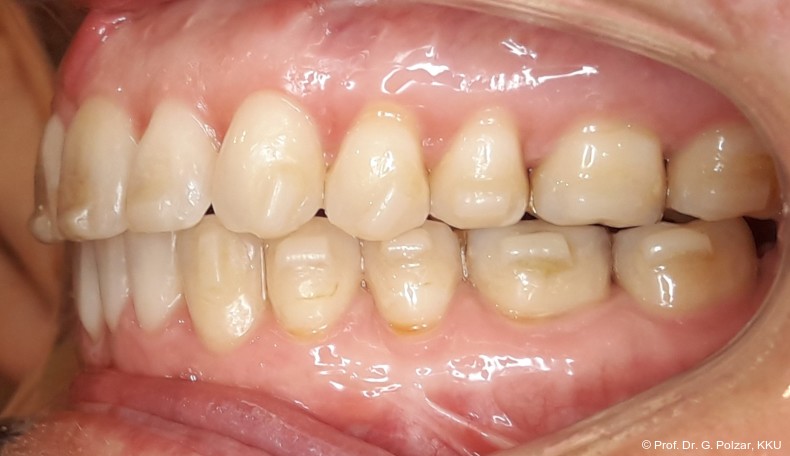

Die 38-jährige Patientin stellte sich 2019 zum ersten Mal in der Praxis vor. Nach einer drei­jährigen kieferorthopädischen Behandlung im Jugendalter mit Multibandapparaturen kam es im Laufe der Zeit zu einem Rezidiv mit Retro­inklination der oberen mittleren Frontzähne. Der Wunsch der Patientin war es, „wieder gerade Zähne“ zu haben. Die sehr gesundheitsbewusste Patientin hatte sich im Vorfeld von 14 kieferorthopädisch tätigen Kollegen beraten lassen, war aber von den vorgeschlagenen Therapiemaßnahmen nicht überzeugt (Abb. 1a–d).

Der intraorale Befund zeigte eine scheinbar neutrale Verzahnung. Trotz Lingualretainer in der UK-Front war ein Engstand in der Unterkieferfront mit leichter Protrusion erkennbar. Appro­ximal des Zahnes 41 waren deutliche schwarze Dreiecke zu erkennen, zudem wies der Zahn eine leichte gingivale Rezession auf (Abb. 3a–f).